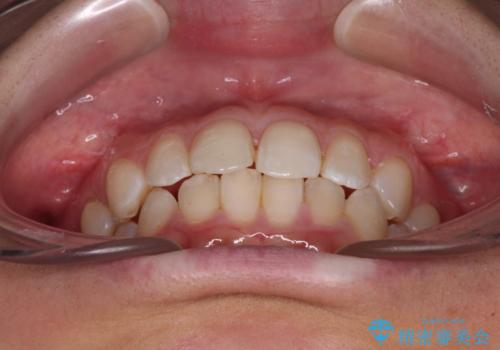

- 前歯のデコボコと歯肉に埋もれている奥歯を気にして来院された患者様です。

インビザラインでの治療を希望されていましたが、左右の下顎大臼歯が歯肉に埋もれており、特に右側は歯軸が顕著に傾斜していたため、インビザライン単独での治療は困難と判断し、ワイヤー装置を併用することとしました。

ワイヤー装置での下顎臼歯改善には時間がかかることが予想されたため、下顎のワイヤー矯正と並行して上顎をインビザラインで整え、その後インビザラインにより上下歯列を整える矯正治療を行うこととしました。

ワイヤー装置を併用したことで、レントゲン写真からも分かるとおり歯軸をしっかりと改善させることができました。